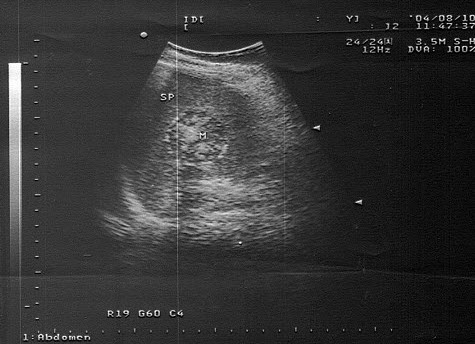

10、单项选择题

男,11岁,右侧阴囊空虚,左侧睾丸可触及,右侧腹股沟区可探及低回声肿块,如图所示,考虑为()

A.隐睾

B.淋巴结

C.腹股沟疝

D.腹股沟肿瘤

E.以上都不是